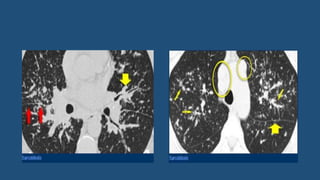

• NSIP pattern on HRCT

• Predominance in the peripheral, posterior, and basal lung regions, with a

concentric distribution.

• Sparing of the immediate subpleural lung (seen in 50% of cases), a finding

that is highly predictive of NSIP

• GGO in cellular NSIP

• Reticulation

• Traction bronchiectasis (usually but not always in fibrotic NSIP)

• Rare honeycombing, which, if present, is of limited extent